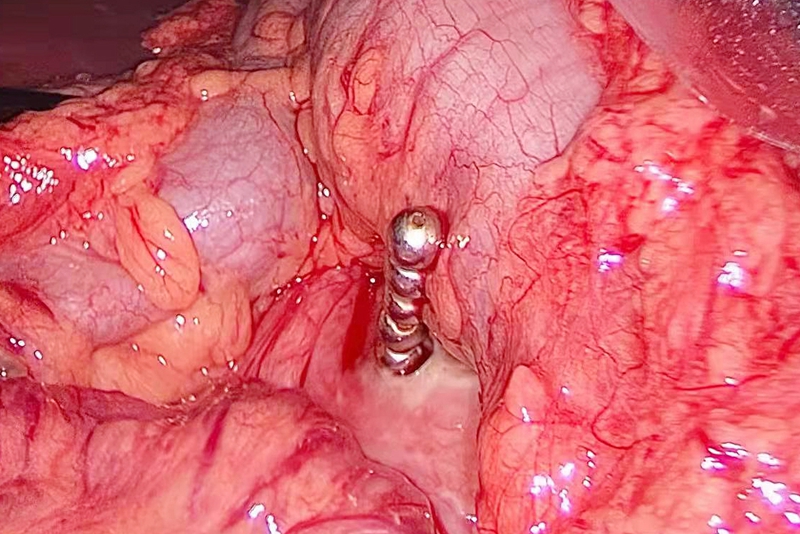

术中,通过微创腹腔镜探查,医生在患者胃内陆续探查到20颗磁力珠。

其中在胃大弯后壁,发现有5颗磁力珠已经突破胃壁进入腹腔,不仅造成胃穿孔,还引发肠壁充血水肿。于是,在取出磁力珠后,又进行了胃穿孔修补术。

“磁力珠磁性很强,太用力分离,反而可能加重肠壁损伤。”整场手术耗时两个多小时,才顺利完成。